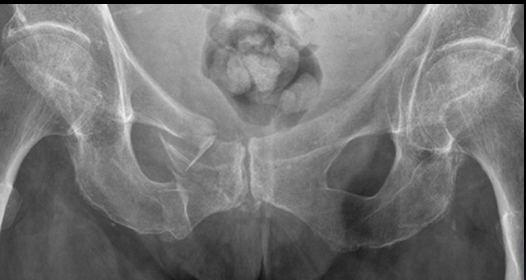

What is represented by 1 and 2 in the AP pelvic radiograph?

1. sacrum

a. ala

b. foraminae

2. sacroiliac joint

What is represented by 3 and 4 in the AP pelvic radiograph?

3. ilium

a. crest

b. ASIS

c. AIIS

4. ischium

a. spine

b. tuberosity

What is represented by 5 in the AP pelvic radiograph?

5. pubis

a. body

b. superior ramus

c. inferior ramus

d. symphysis

What is shown here?

Which age group is usually affected?

fracture of the superior and inferior pubic rami on the right-hand side

common in elderly patients through trips, low-energy falls

What condition is shown here?

diastasis of the pubic symphysis

this is where the pubic symphysis is wider than it should be